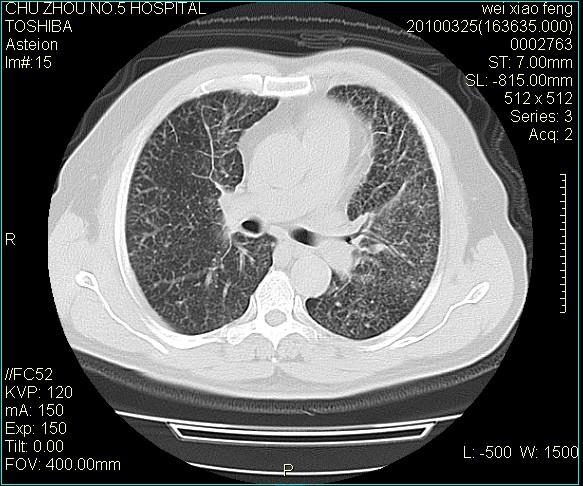

标题: CT25347:男,60岁,反复咳、痰、喘3月,加重3天。诊断??? [打印本页]

男,60岁,反复咳、痰、喘3月,加重3天。

双肺间质性改变。

考虑双肺血型潘散肺结核/

间质性肺炎伴间质纤维化!不排除伴有职业病!

双肺间质纤维化,双肺血型潘散肺结核。

考虑间质性肺炎伴间质纤维化。

右肺中叶结节影为原发灶,考虑右肺中叶周围型肺癌并淋巴道转移